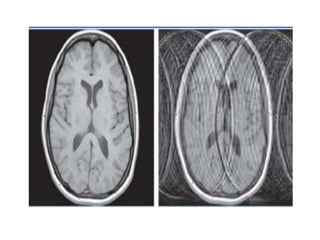

Partial volume artifact

The signal intensity of different tissues and structures

that are located in the same voxel are averaged.

Remedy

use thinner slice thickness

Axial T1WI of the brain at exactly the same level. Second image shows 7th and 8th cranial nerves (arrow) but the first one merely depicts them.

The reason for this is the partial volume averaging. The first slice was taken at thickness of 10 mm while second slice was taken at 3 mm.

Partial volume artifact Thesignal intensity of different tissues and structures that are located in the same voxel are averaged. Remedy use thinner slice thickness

Axial T1WI ofthe brain at exactly the same level. Second image shows 7th and 8th cranial nerves (arrow) but the first one merely depicts them. The reason for this is the partial volume averaging. The first slice was taken at thickness of 10 mm while second slice was taken at 3 mm.